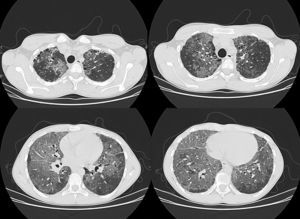

En el momento del ingreso en la unidad de neumología el paciente presentaba disnea basal gradoi-ii. A la exploración se apreciaba buena coloración de la piel y de las mucosas y acropaquías. La saturación basal de O2 era del 93% y la auscultación mostraba buen murmullo vesicular, sin ruidos sobreañadidos. La espirometría mostró FEV1: 44%, FVC: 47%, FEV1/FVC:79, MMEF:29%, si bien la colaboración del paciente fue incompleta. La radiografía de tórax mostraba extenso patrón alveolointersticial bilateral con afectación multilobar. Durante la hospitalización se completó con tomografía computarizada de alta resolución (TACAR), en la que se observó marcada alteración del parénquima pulmonar, con extensas áreas en vidrio deslustrado distribuidas por todos los lóbulos aunque con predomino basal, sobre el que se superponía engrosamiento septal, conformando un patrón en empedrado o crazy-paving (fig. 1). Además se apreciaban áreas de panalización en el parénquima pulmonar subpleural a nivel de ambos lóbulos superiores, aunque de predominio derecho.

Los hallazgos radiológicos en TACAR más frecuentes en la NL son4,5: presencia de condensación de bajo coeficiente de atenuación (entre –75 y –35UH), muy específica y frecuente en la NL endógena1, opacidades en vidrio deslustrado, patrón en empedrado (crazy-paving) y presencia de opacidades centrolobulillares. Además, en ella la afectación pulmonar tiene un predominio basal4.

El patrón en empedrado se describió inicialmente en la proteinosis alveolar4, si bien posteriormente se ha comprobado que puede aparecer en multitud de procesos, como en la sarcoidosis, la neumonía intersticial no específica, la neumonía organizada (tanto en la neumonía organizada criptogenética como en la bronquiolitis obliterante con neumonía organizada), infecciones pulmonares (principalmente víricas y por micoplasma), neoplasias como el carcinoma bronquioalveolar, la hemorragia, el edema pulmonar y la NL.